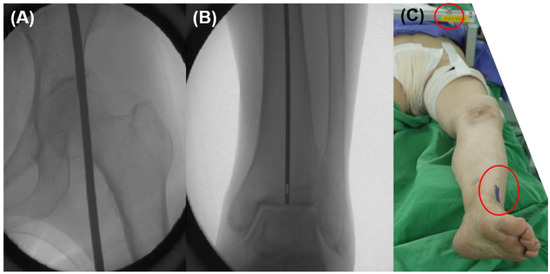

2.4. Intraoperative Planning

2.5. Operative Procedure